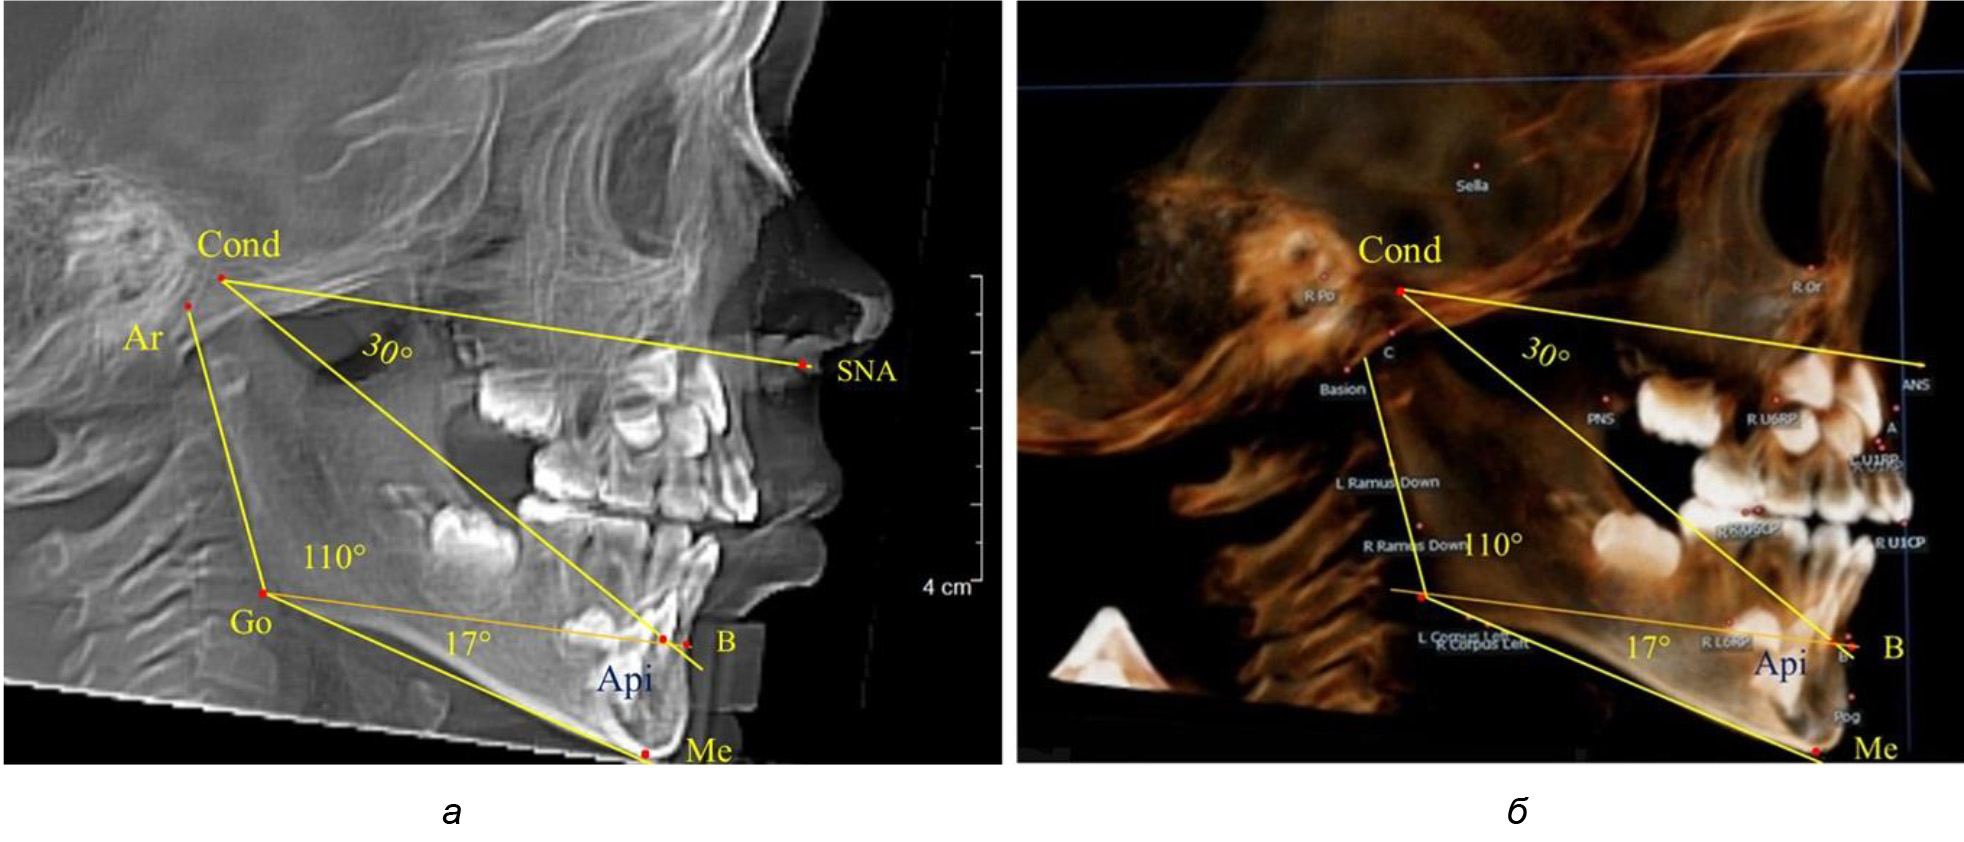

Таким образом, в периоде молочного прикуса с оптимальными окклюзионными соотношениями, несмотря на линейные размеры в вертикальном и сагиттальном направлении, которые, безусловно, меньше параметров взрослых людей, величина основного угла гнатической части лица SNA-Cond-Api соответствовала параметрам людей с полностью сформированным физиологическим прикусом постоянных зубов. Анализируя данные рентгенограмм детей в периоде сменного прикуса, отмечено, что величина основного угла гнатической части лица SNA-Cond-Api, так же как в молочном и постоянном прикусе, в норме составляла от 28 до 32°. В то же время угол нижней челюсти и его составляющие отличались вариабельностью параметров при различных показателях нижнечелюстного угла. Достоверных различий угла гнатической части после смены нижних медиальных резцов и прорезывания первых постоянных моляров (4 ребенка) не было; происходил очередной этап подъема высоты прикуса и увеличение линейных размеров костей гнатической части, однако угловые параметры были относительно стабильны. После смены всех резцов и замены первых молочных моляров первыми премолярами (6 человек) увеличивались линейные размеры при сохранившихся угловых показателях гнатической части лица (рис. 5).

Рис. 5. Варианты ТРГ после прорезывания ППМ и нижних резцов (а), всех резцов и первых премоляров (б)

Таким образом, в период сменного прикуса с оптимальными окклюзионными соотношениями, несмотря на увеличение линейных размеров в вертикальном и сагиттальном направлении, по сравнению с прикусом молочных зубов, величина основного угла гнатической части лица SNA-Cond-Api соответствовала показателям как постоянного, так и молочного прикуса с физиологическими окклюзионными соотношениями.